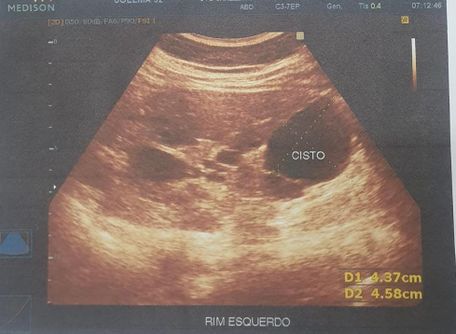

Foi realizado exame de imagem (21/10/2024), ultrassonografia abdominal com os seguintes achados (figura 1.1, 1.2, 2 e 3) Exames laboratoriais (21/10/2024): Acido úrico 2 mg/dl, Bilirrubina total 0,37 mg/dl, Bilirrubina direta 0,18 mg/dl, Bilirrubina indireta 0,19 mg/dl, TGP 21 u/l, TGO 16 U/L, Uréia 34 mg/dl, Creatinina 0,51 mg/dl, Sorologia para hepatite B, C não reagente.

Figura 2 e 3. Rim esquerdo ,apresenta tamanho aumentado , parenquima heterogêneo e contornos irregulares, com dimensoes 13.1 cm x 5.3 cm. Multiplos cistos em ambos os rins, o maior no polo inferior do esquerdo medindo 4.6 cm x 4.4 cm. Rim direito , apresenta tamanho aumentado, parenquima heterogêneo e contornos irregulares, dimensoes 12.0 cm x 5.1 cm.